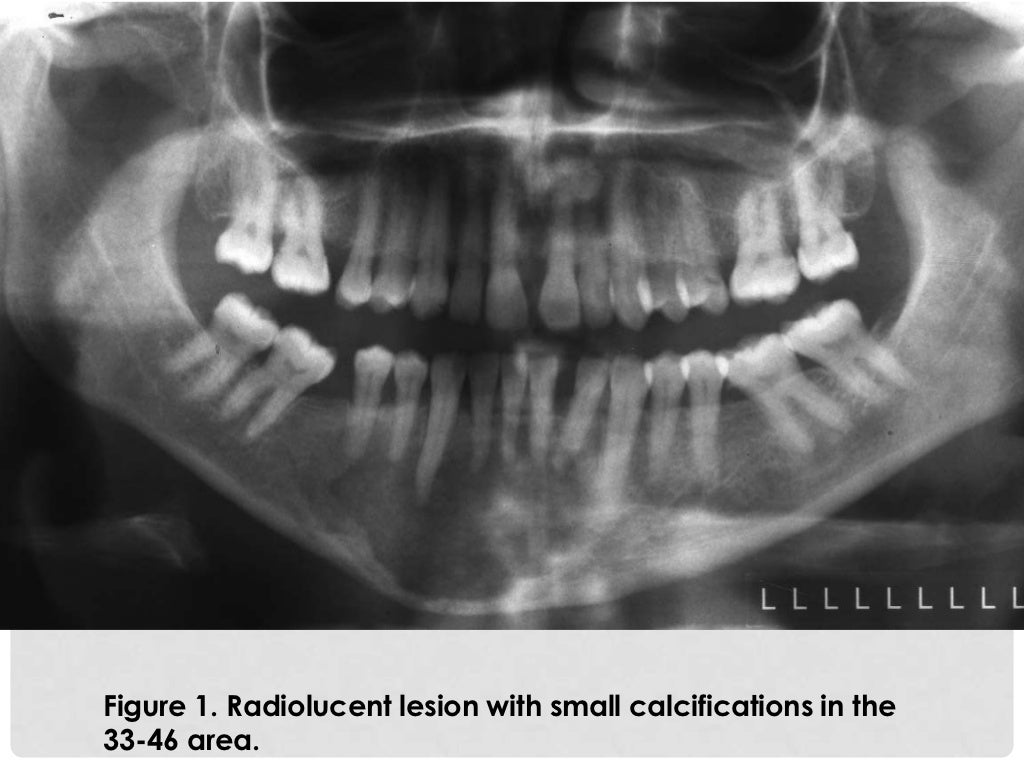

Osteoid osteoma in the mandible Case report Issuu Osteoma Dental Slideshare Osteoma is a slow growing benign tumor consisting of well differentiated compact. Benign neoplasms of bone forming tissue. Osteoma is a benign osteogenic tumor composed of cancellous or compact bone, classified as peripheral, central, or. Se presenta como una masa ósea. Osteoid osteoma of the maxilla may present as pain related to dental implants, and careful radiographic assessment of the. Osteoma Dental Slideshare.